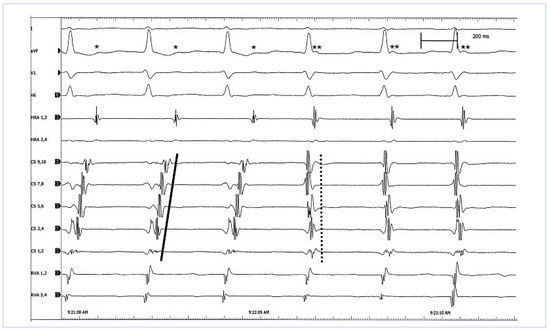

Prevalence, Mechanism and Management of Atrial Fibrillation in Athletes

by Naiara Calvo and Lluís Mont

Atrial fibrillation (AF) is the most commonly encountered arrhythmia in clinical practice with an estimated prevalence of 0.4% to 1% in the general population [1], increasing with age to 8% in those older than 80 years [2]. The recognised risk factors for developing AF include age, structural heart disease, hypertension, diabetes mellitus and hyperthyroidism [3]. However, the mechanisms underlying the onset and maintenance of AF in patients younger than 60 years in whom no cardiovascular disease or any other known causal factor is present are yet to be clarified. This condition is termed lone AF [4], and may be responsible for as many as 30% of patients with paroxysmal AF seeking medical attention [5, 6]. It is well known that regular exercise is beneficial to health and reduces the risks of cardiovascular diseases [7, 8]. However, recent studies suggest that longterm endurance exercise may increase the incidence of AF [9–16]. This review article is intended to analyse the possible links between AF and endurance sport practice, the pathophysiological mechanisms responsible for this association and the recommended therapeutic options. Full article

Figure 1